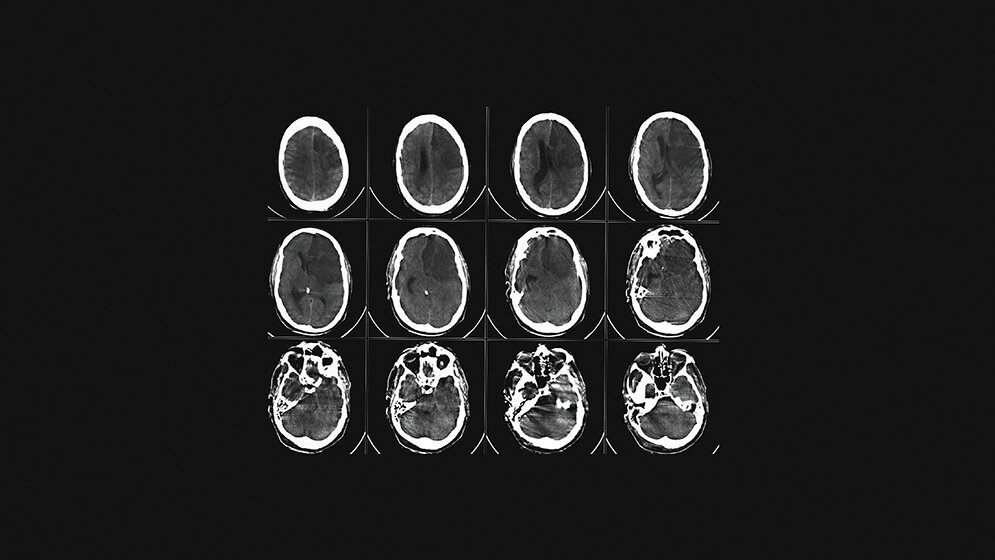

Die dritthäufigste Todesursache in Deutschland ist der Schlaganfall. Jedes Jahr sind Tausende Menschen davon betroffen. Zeit spielt bei diesem Thema die wichtigste Rolle überhaupt, denn es geht um nichts Geringeres als um das Gehirn des Menschen, dem Ursprungsort des Denkens, des Fühlens, der Persönlichkeit jedes Einzelnen. Symptome treten häufig unspezifisch auf, werden nicht rechtzeitig erkannt und mitunter unterschätzt. Hängende Mundwinkel, Wortfindungsstörungen, die Zeitung nicht richtig lesen können, sich komisch fühlen, plötzliche Kopfschmerzen oder für einen Moment nicht wissen, wo man sich befindet. Schon Minuten bis wenige Stunden nach Auftreten der ersten Symptome können bleibende Schäden zurückbleiben oder gar der Tod eintreten. Auf dem schnellsten Weg muss der Patient in eines der zertifizierten Krankenhäuser gebracht werden, um keine Zeit zu verlieren. Die Radiologische Diagnostik spielt eine immense Rolle. Deutschland ist mit etwa 350 zertifizierten Stroke Units flächendeckend gut aufgestellt, dennoch muss ständig an einer Verbesserung gearbeitet werden. Die Computertomografie ist bei den bildgebenden Verfahren noch die Untersuchungsmethode der ersten Wahl, da sie schnell verfügbar und von den meisten technischen Mitarbeitern bedient werden kann. Das MRT bietet hier zwar Vorteile in Bezug auf die Sensitivität, jedoch bilden die Liegezeiten, der Zustand des Patienten und die Erfahrung in der Auswertung und Bedienung, vor allem im Bereitschaftsdienst auf technischer und ärztlicher Ebene, große Hürden.

The third most common cause of death in Germany is stroke. Every year, thousands of people are affected. The time is very important because it is about nothing less than the human brain that is in danger, the place of origin of thought, feeling and personality. Symptoms often appear unspecified, are not recognized in time and are sometimes underestimated for example facial droop, word finding disorders, not being able to read the newspaper properly, feeling strange, sudden headaches or not knowing where you are for a moment. Minutes to a few hours after the onset of the first symptoms, permanent damage may remain or even death may occur. It is very important to take the patient to one of the certified hospitals in order not to lose any time. Radiological diagnostics plays an immense role. Germany is well positioned with about 350 certified stroke units throughout the country, but an improvement still has to be made all the time. Computer tomography is currently the examination method of choice for imaging procedures because it is quickly available and can be operated by most technical staff. Although MRI offers advantages in terms of sensitivity, the length of stay, the patient‘s condition and experience in evaluation and operation, particularly on-call service at the technical and medical level, pose major hurdles.